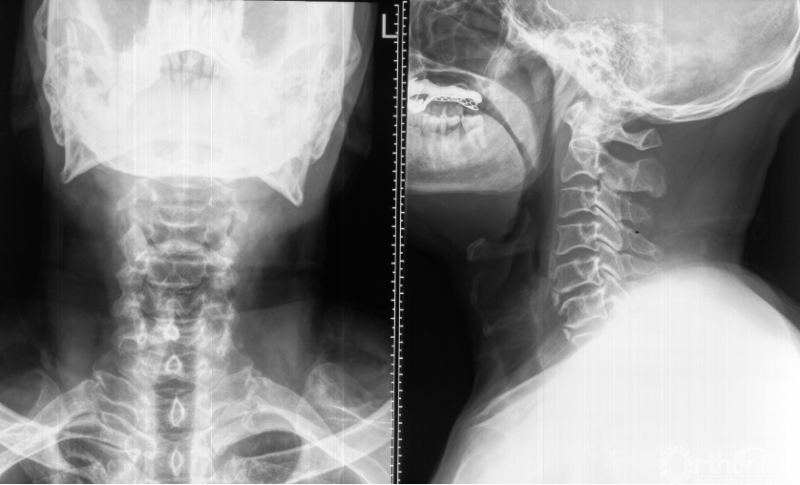

心电图提示窦性心律,ST-T轻度压低。胸部X线、胸部CT、心脏彩超及心肌酶均未见明显异常。颈椎X线提示颈椎退变及前纵韧带骨化(图A),颈椎MRI提示C7-T1椎间盘突出导致右侧C8神经根严重压迫(图B)。经科室讨论明确诊断为神经根型颈椎病及颈源性胸痛后,进行C7/T1的ACDF手术(图C),术后患者胸痛症状明显好转(VAS=2分),右手麻木症状消失,肌力也逐渐恢复。

图A 术前颈椎正侧位